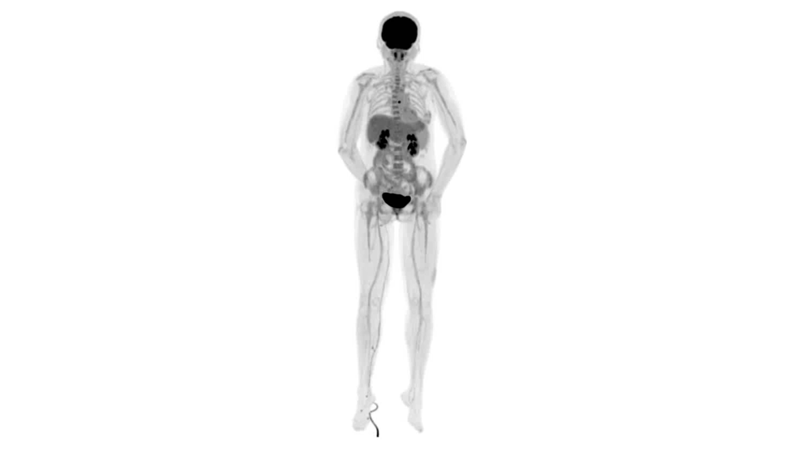

目前聯(lián)影在PET-CT領(lǐng)域的主要產(chǎn)品有:96環(huán)光導(dǎo)PET-CT和uExplorer探索者。其中,uExplorer探索者是由聯(lián)影與美國(guó)分子影像科研聯(lián)盟探索者共同研發(fā)的。uExplorer探索者是世界首臺(tái)全景掃描PET-CT,長(zhǎng)達(dá)2米,繼承了聯(lián)影PET家族的優(yōu)秀基因——具備業(yè)界最高2.8mm空間分辨率與先進(jìn)的飛行時(shí)間(Time of Flight,TOF)技術(shù)。

可4D呈現(xiàn)體內(nèi)藥物實(shí)時(shí)代謝情況,讓全身藥效可視化,全方位評(píng)估療效,加速藥物研發(fā);可精準(zhǔn)定位腫瘤位置,監(jiān)控腫瘤微轉(zhuǎn)移,助力定點(diǎn)靶向治療,讓腫瘤無(wú)處可藏;科研探索領(lǐng)域,以代謝信息判斷神經(jīng)膠質(zhì)細(xì)胞變化,讓細(xì)胞“開(kāi)口說(shuō)話(huà)”,助力多器官神經(jīng)關(guān)聯(lián)研究…

uExplorer探索者不再局限于傳統(tǒng)靜態(tài)代謝過(guò)程3D成像,而是在此基礎(chǔ)上新增一個(gè)維度——時(shí)間,從而實(shí)現(xiàn)4D全景成像。

注射總劑量為7.8mCi,14分鐘全身采集時(shí)間,在擁有超高靈敏度與超高分辨率的uEXPLORER上,即可得到展示顯示人體諸多精細(xì)結(jié)構(gòu)的高清三維圖像。